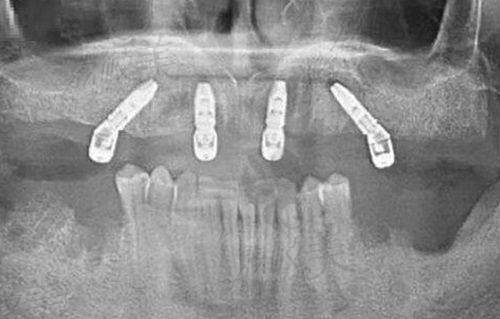

王医生擅长“不开刀也能种牙”。无论是即拔即种、穿颧穿翼、无牙颌种植,还是看起来“高冷复杂”的上颌窦提升、骨量不足的骨增量手术,他都能用“数字化微创”技术化繁为简。具体擅长的包括:

✔ 微创即刻种植(拔牙当天种牙)

✔ 全口/半口无牙颌All-on-4/6快速修复

✔ 高难度骨增量、骨移植